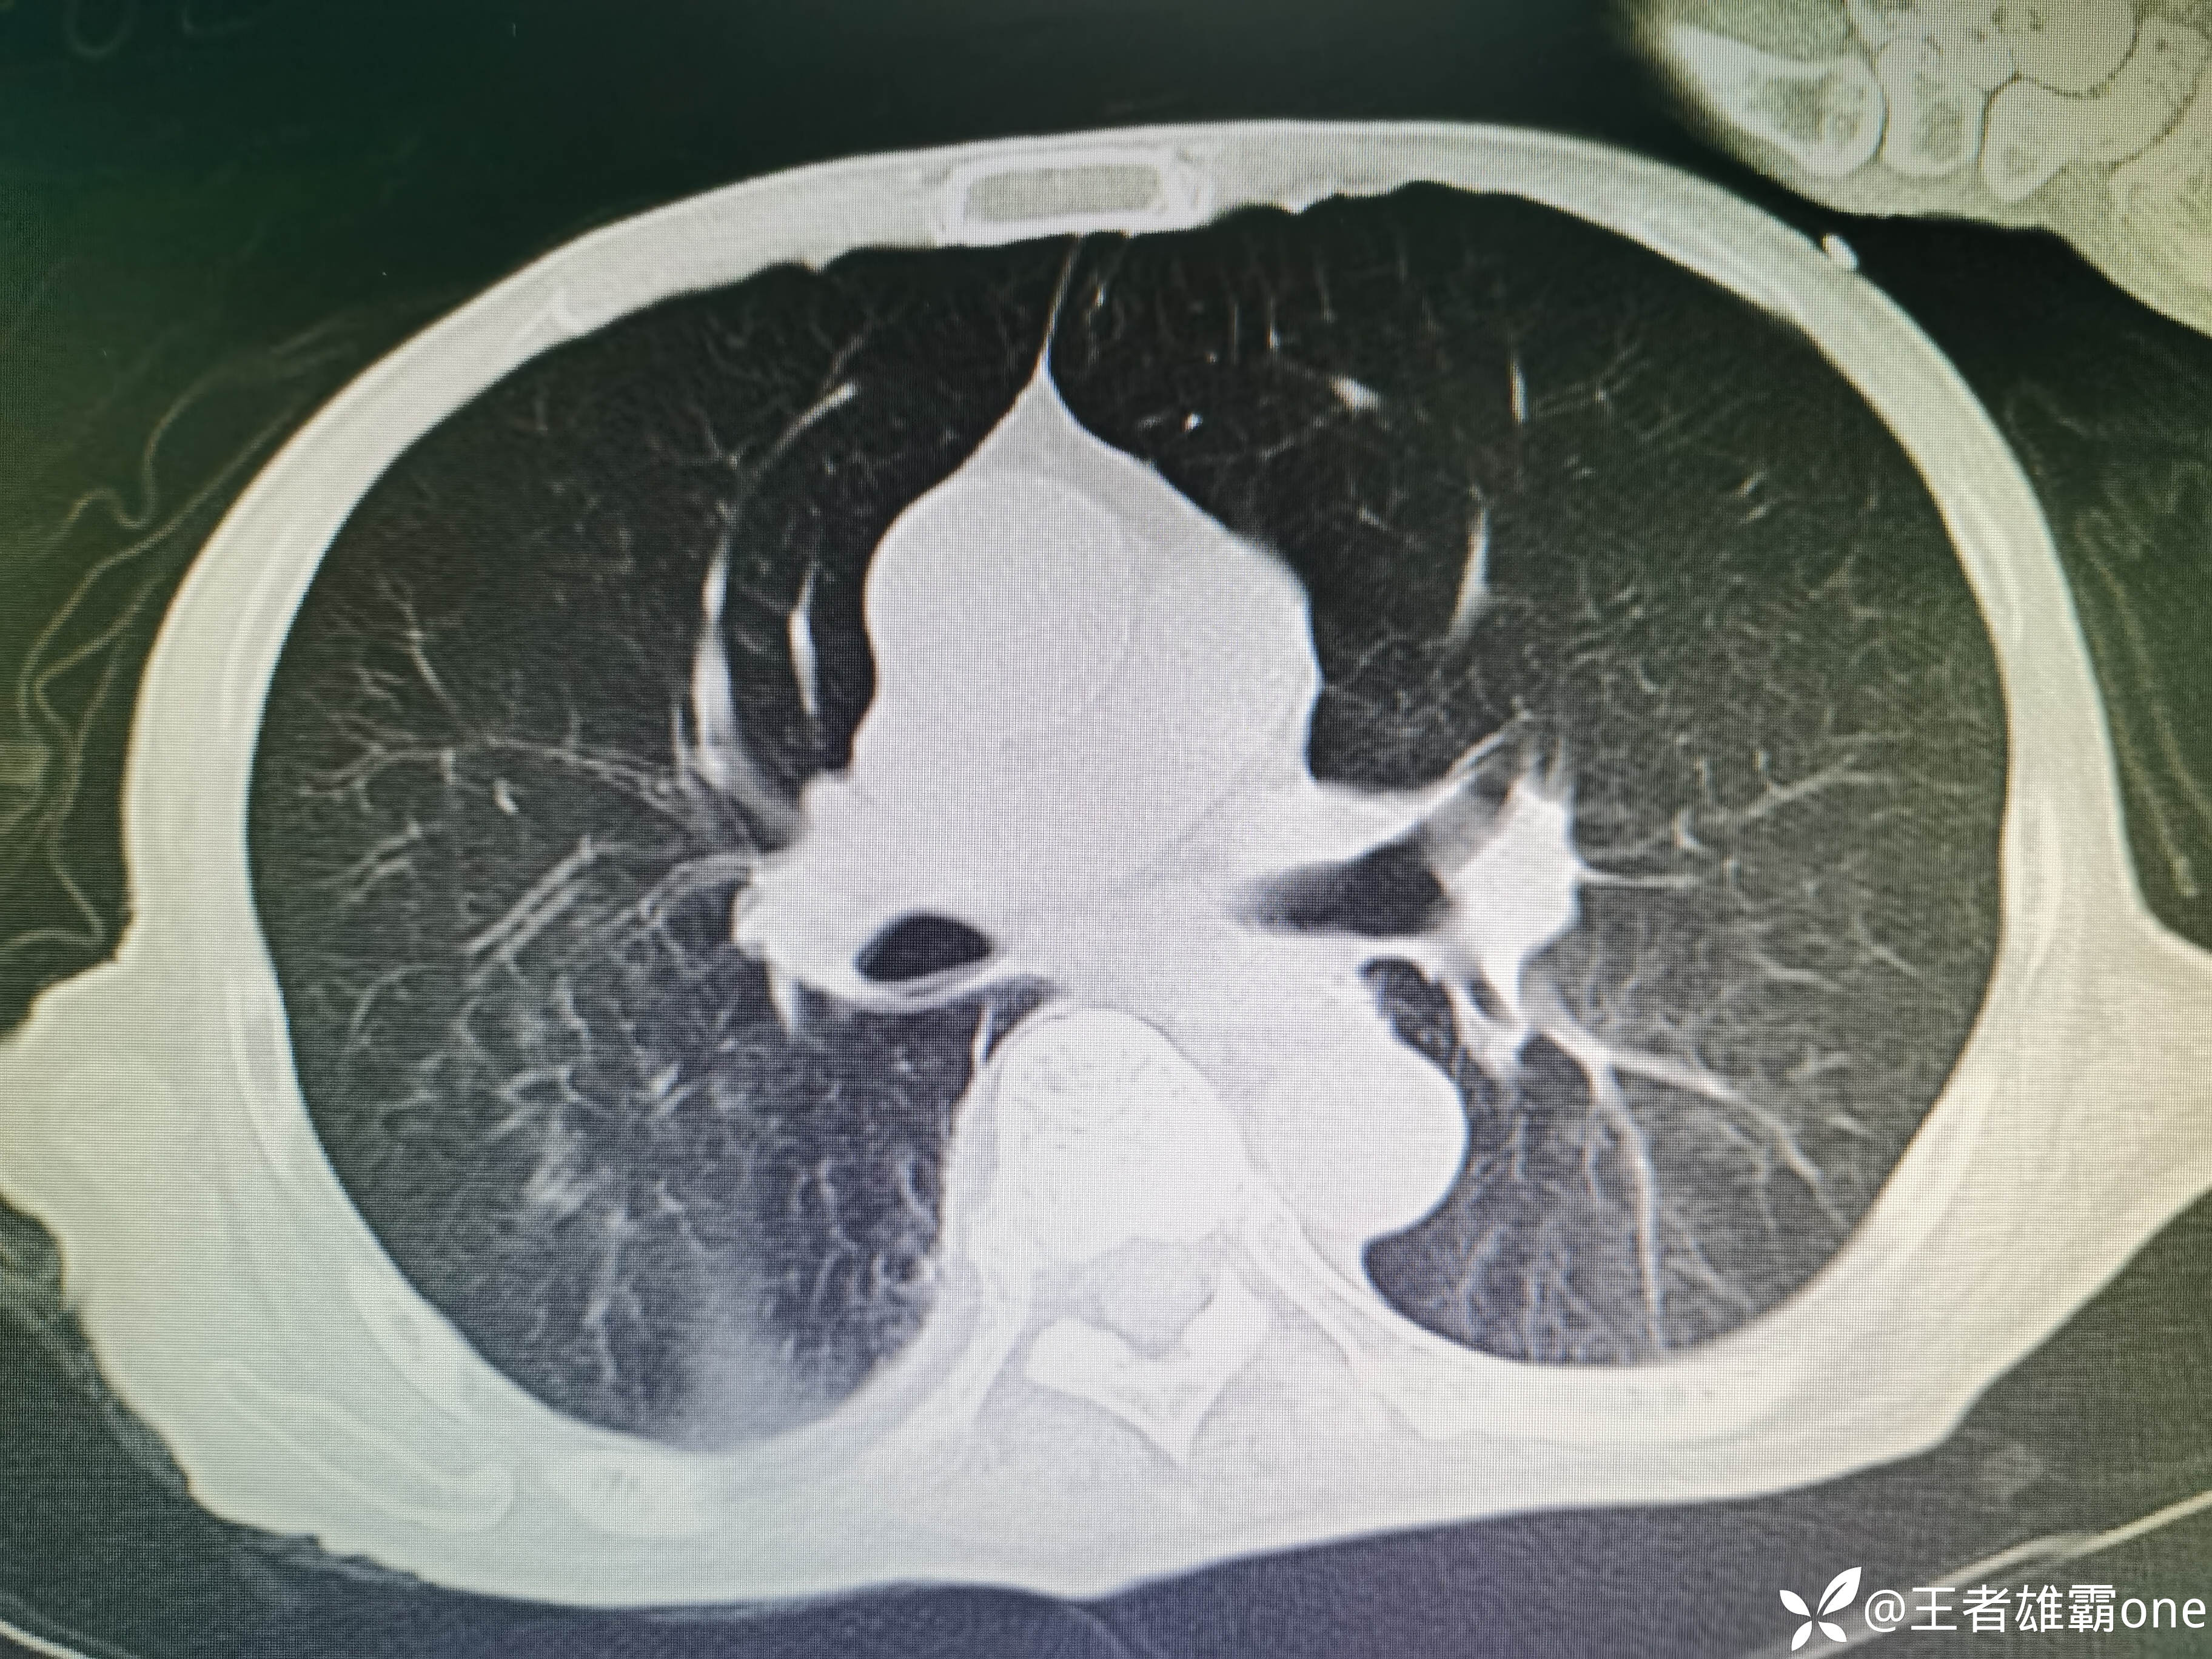

入院时胸部CT:

具体图片: